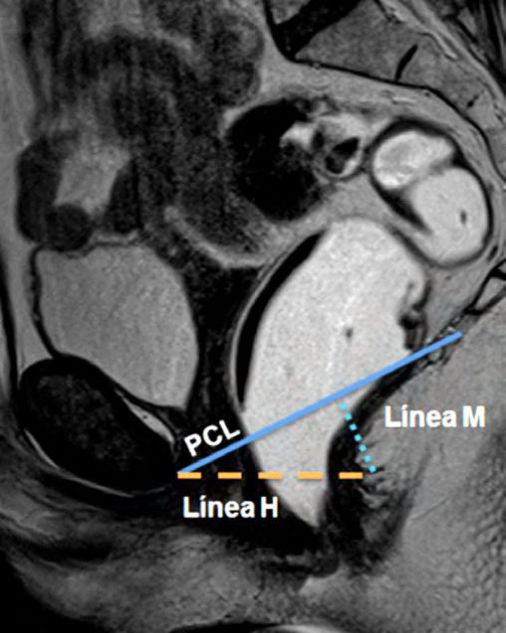

Figura 2

Líneas de referencia. Imagen de la línea media potenciada en T2 en el plano sagital, durante el reposo. Se trazaron la línea PCL (línea continua azul), línea H (línea punteada naranja) y línea M (línea punteada celeste). El músculo puborectal se topografía inmediatamente por detrás de la unión ano-rectal y el plano del elevador es paralelo a la línea PCL.

La valoración del piso pélvico se hace mediante la valoración morfológica, el sistema HMO y el ángulo ano rectal (Ver figuras 1, 2 y 3) (1)

La valoración morfológica se realiza con secuencias potenciadas en T2 de alta resolución, que permiten un estudio anatómico detallado de los órganos de la pelvis. El sistema HMO constituye un método estandarizado creado para caracterizar y documentar el prolapso y relajación del piso pélvico, que se basa en el trazado de tres líneas fundamentales.

La línea pubococcígea (PCL) se extiende desde el borde inferior del pubis a la última articulación coccígea y representa el nivel de piso pélvico, constituyendo la línea de referencia a partir de la cual se miden los prolapsos, tanto en reposo como en Valsalva.

La línea H se traza desde el borde inferior del pubis hasta la pared posterior del recto a la altura de la unión ano rectal, representando el diámetro anteroposterior del hiato urogenital, con un valor normal menor a 6 cm (Ver figuras 4).

La línea M es perpendicular a la PCL a nivel del sector más posterior de la línea H y representa el descenso del hiato del elevador, con un valor normal menor a 2 cm. El ángulo ano rectal es el ángulo entre el eje central del canal anal y la pared posterior del recto, con un valor normal entre 108º y 127º y una variación de hasta 15º en Valsalva.

Se describe una línea adicional llamada línea media púbica (MPL) que se traza caudalmente siguiendo el eje mayor de la sínfisis del pubis. Esta línea corresponde al nivel del himen vaginal, el cual es utilizado históricamente como punto de referencia para la valoración clínica. 12-13